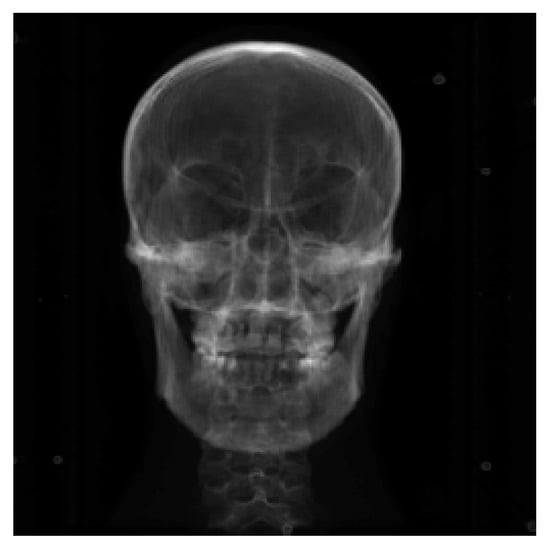

The DICOM sequence obtained from the human brain model’s CT scan is used as a 3D floating image in the registration experiment. The projection image (DRR) under specific CT parameters is used as a 2D reference image to simulate a real X-ray image. The size of the CT image is 512 × 512 × 283, the voxel spacing is 0.7813 × 0.7813 × 1.0, and the unit is mm. The projected image size is 512 × 512, the pixel spacing is 0.5 × 0.5, and the unit is mm. The 3D screenshot of the CT image is shown in Figure 1, and the 3D model rendered by the CT image is shown in Figure 2.

Figure 1. Three dimensional CT of the brain model.

The Powell optimization algorithm’s one-dimensional search accuracy in the experiment is set to 0.01. The algorithm’s overall iterative accuracy is set to 0.001, and the maximum number of iterations is set to 1000. For the original resolution image registration, three groups of experiments are set up, and the rigid body transformation parameters are arranged according to the order ( α , β , θ , t x , t y , t z ) . The first three parameters are rotation along the X-, Y-, and Z-axes. The last three parameters are translation along the X-, Y-, and Z-axes. The true values of the first group of experimental reference images are set to (−3,4,2,5,5,5). The second group of experimental reference images is set to (−3,4,2,10,10,10). Finally, the third group of experimental reference images is set to (5,6,7,8,9,10). In the experiment, the initial value is optimized by (0,0,0,0,0,0). As shown in Figure 5, the DRR image projected by CT at the initial value is shown. The reference images of the three groups of experiments are shown in Figure 6a–c and correspond to the reference images of experiment 1, experiment 2, and experiment 3, respectively.

Figure 5. DRR image at the initial value.